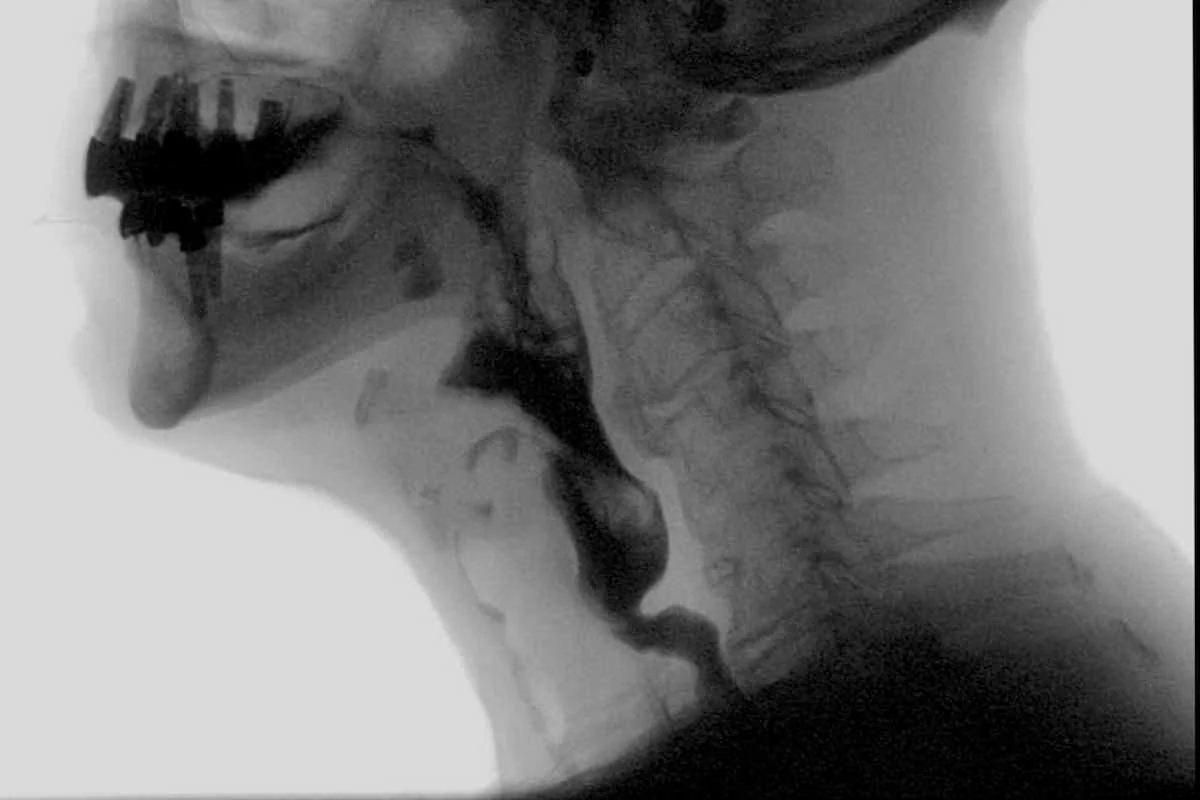

MODIFIED BARIUM SWALLOW STUDY (MBSS):

• Patient is exposed to radiation

• MBSS is time-limited due to radiation exposure

• Provides view of esophagus